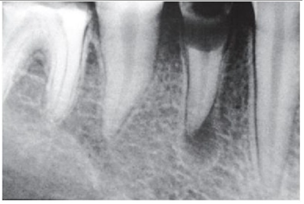

A fase de instrumentação, considerada uma das

etapas cruciais no processo químico-mecânico

de preparo dos canais radiculares, visa alcançar

um formato cônico para o canal radicular

(modelagem) com diâmetros aumentados ao

máximo possível.

Ao realizar a instrumentação de um canal radicular com curvatura, é possível identificar três regiões com maior desgaste das paredes dentinárias, o que pode resultar em acidentes ou complicações indesejáveis. Observando a imagem abaixo, marque a alternativa que indica corretamente os pontos identificados como 1, 2 e 3.